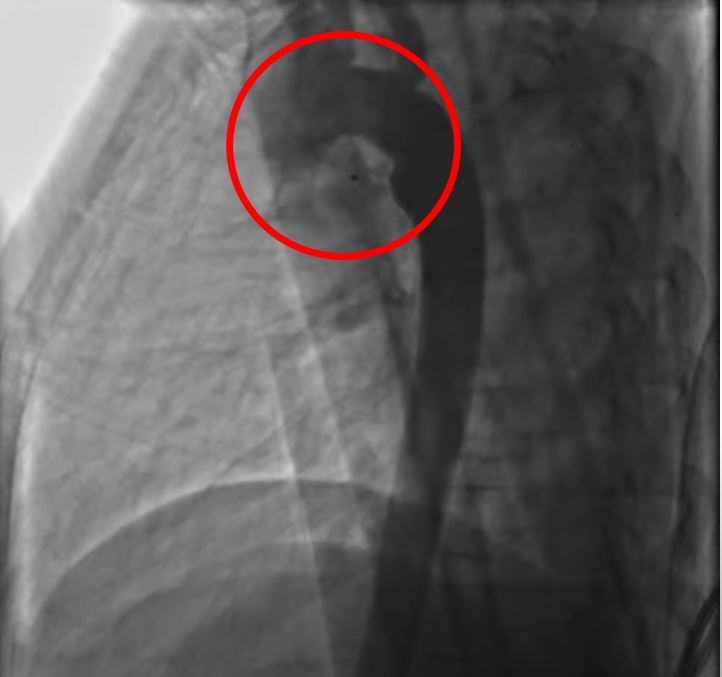

• (花蓮慈院提供)開放性動脈導管術後

花蓮一名兩歲男童被診斷出有「開放性動脈導管」,經花蓮慈濟醫院兒童急重症科以心導管治療後,讓男童恢復健康。小兒心臟科醫師裘品筠表示,大部份開放性動脈導管,已可運用心導管的技術關閉,很少需要開刀治療。

目前治療方式分為藥物治療、心導管治療、手術治療等三種,有症狀的早產兒或動脈導管無法關閉的足月兒,可使用藥物,讓動脈導管收縮變小,或給予抗心衰竭藥物控制症狀,大部份的開放性動脈導管,可運用心導管技術,放置螺旋線圈或關閉器來關閉,很少需要開刀治療。